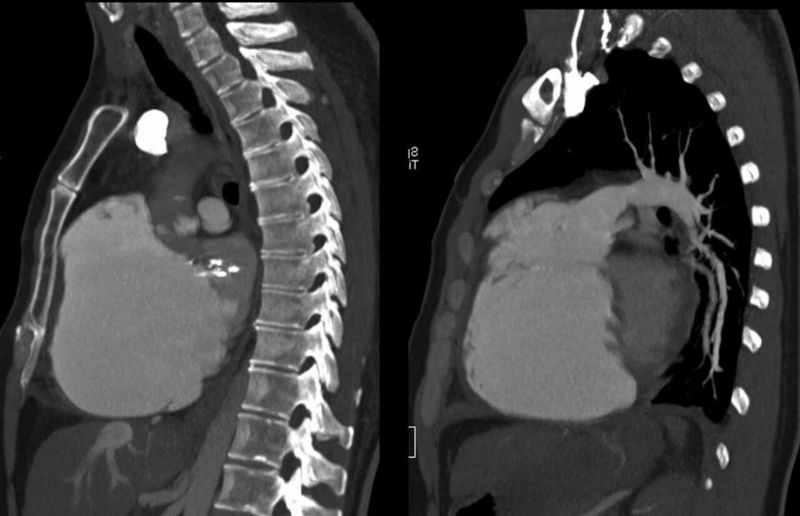

Ebstein Anomaly

Sir can you please tell what exactly is the positive finding here?

enlargement of heart